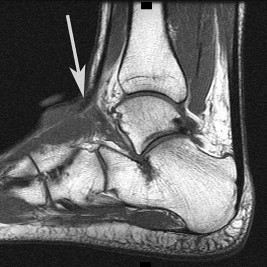

Figures 15a through 15c are the radiograph and MR images of a 16-year-old girl who experienced posterior knee pain after a dance recital 3 weeks ago; the pain resolved 1 week ago with ibuprofen use. What is the most appropriate treatment for this patient?

The images reveal a small reactive-type lesion in the posteromedial aspect of the distal femur consistent with an avulsive cortical irregularity. Also referred to as a cortical desmoid, periosteal desmoid, or “tug lesion,” this lesion is seen most commonly in young adolescents, with a slight preponderance in boys, with one-third occurring bilaterally. It is thought to be related to repeated microtrauma from pulling of the adductor magnus or medial gastrocnemius on their respective periosteal attachment sites. Proper treatment involves recognition of this benign disorder without further workup. Often best seen on an oblique radiograph, the lack of soft-tissue mass or bone destruction leads to the benign diagnosis. Serial radiographs typically show complete resolution by age 20.